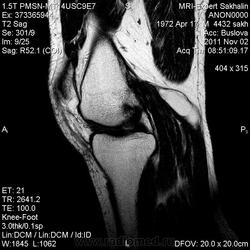

Киста Бейкера.

Просто киста Бейкера.Такого размера пока не встречалась-почти 5.0 см в длину.И , конечно, мениск-по поводу травмы и обратился))))

Хорошо видно кистозное образование.

Да, причем достаточно крупное.

Бывало и больше... Тут то синовиита толком нету...